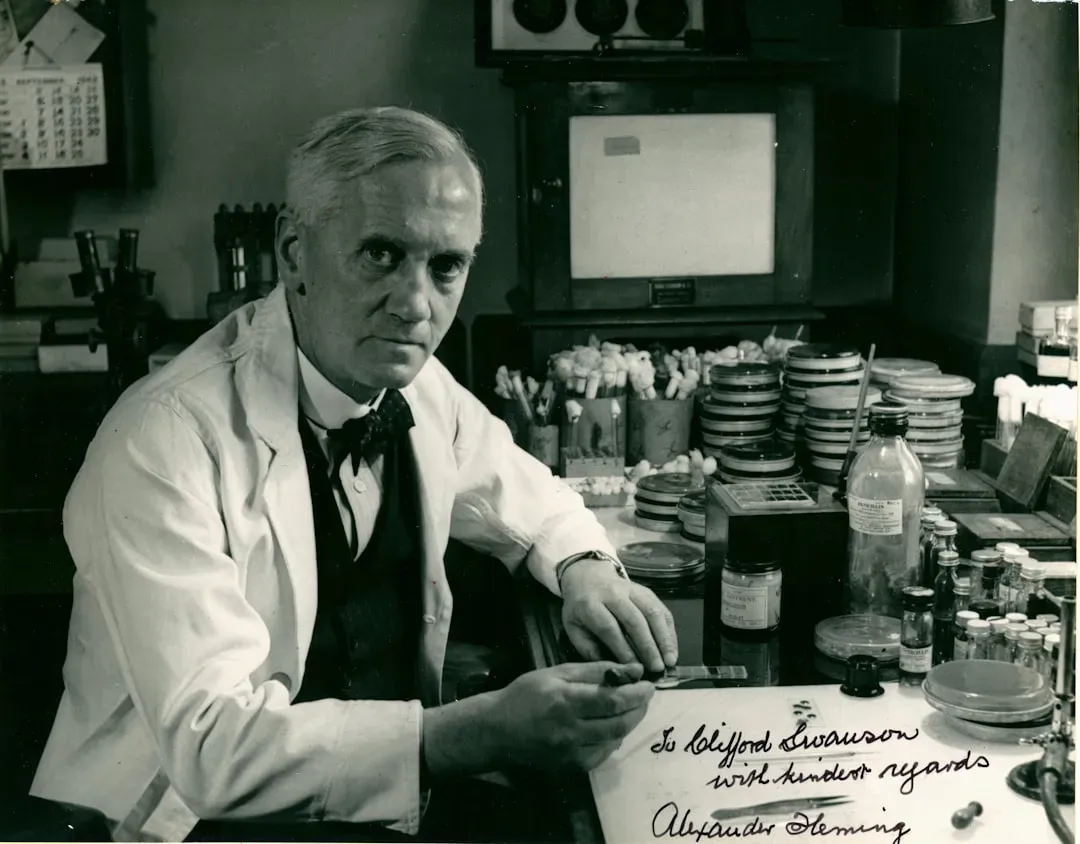

1. Penicillin: The Messy Petri Dish That Saved Millions

Imagine walking into your lab after a vacation, seeing mold contaminating your carefully prepared petri dishes, and instead of throwing them out, leaning closer out of curiosity. That’s essentially what happened to Alexander Fleming in 1928 when he noticed that a strange mold was killing the surrounding bacteria. Most people would’ve called it a failed experiment and moved on, but he saw something different in that messy plate.

What started as contamination became penicillin, the first widely used antibiotic, and it transformed medicine more dramatically than almost any other discovery. Before antibiotics, even a small cut could turn deadly, and surgeries were incredibly risky; after penicillin, survival rates soared and treatments we now consider routine became possible. It wasn’t developed overnight – it took years of refinement and large-scale production, especially during World War II – but the spark was that accidental mold. It’s a good reminder that sometimes the breakthrough is hiding in what looks like a disaster.